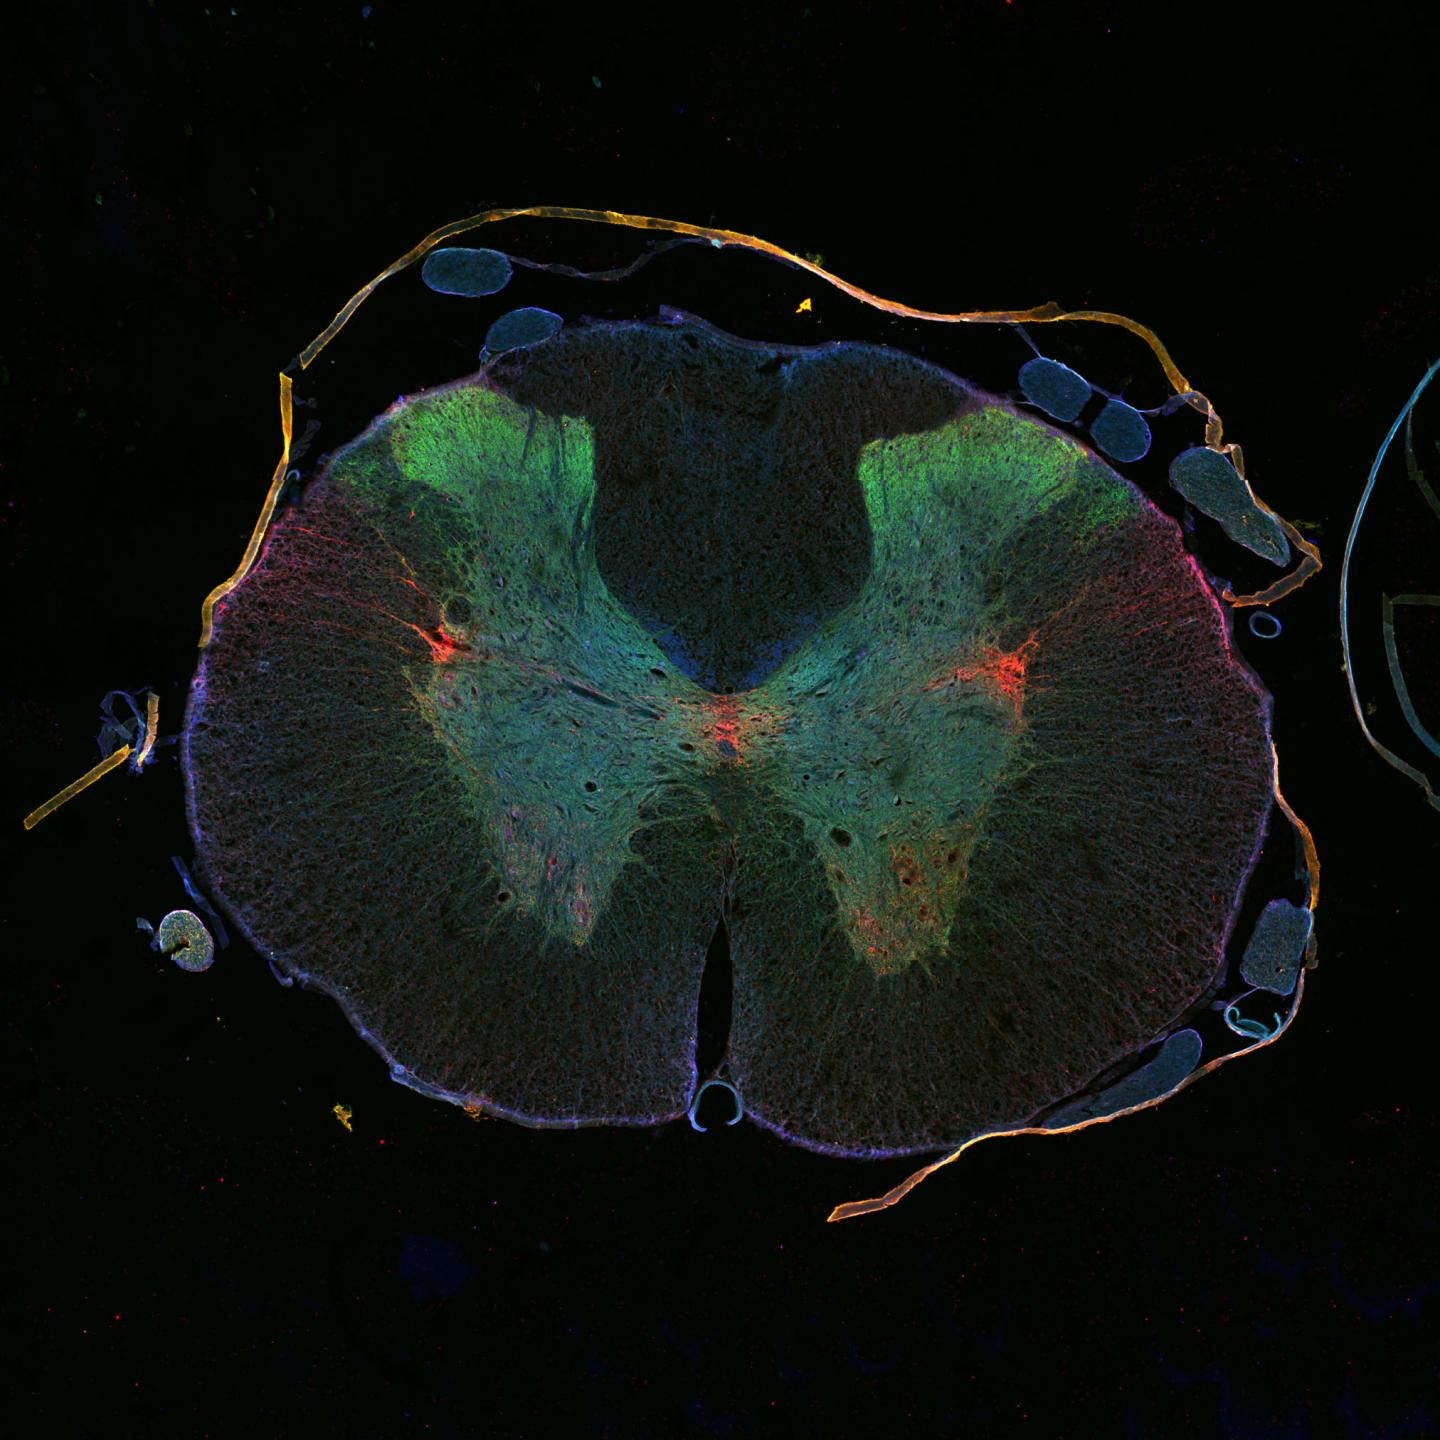

Damage to the spinal cord rarely heals because the injured nerve cells fail to regenerate. The regrowth of their long nerve fibers is hindered by scar tissue and molecular processes inside the nerves. An international team of researchers led by DZNE scientists in Bonn now reports in Science that help might be on the way from an unexpected quarter: in animal studies, the cancer drug epothilone reduced the formation of scar tissue in injuries to the spinal cord and stimulated growth in damaged nerve cells. Both promoted neuronal regeneration and improved the animals' motor skills.

Experiments have shown epothilone works on several levels. Epothilone reduces the growth of scar tissue by inhibiting the formation of microtubules in the cells that form the scar tissue. Therefore they cannot migrate to the spinal cord lesion and cause wound scarring. At the same time, epothilone promotes growth and regeneration in the nerve cells by causing microtubules to grow into the damaged axon tips.

In short: through the same effect, namely microtubule stabilization, epothilone is able to inhibit directional movement in scar-forming cells while stimulating active growth in nerve cell axons. The animals treated with epothilone after spinal cord injury walked better than those that received no treatment, due to improved balance and coordination. The next goal of Bradke and his team is to test the effect of epothilone on various types of lesion.